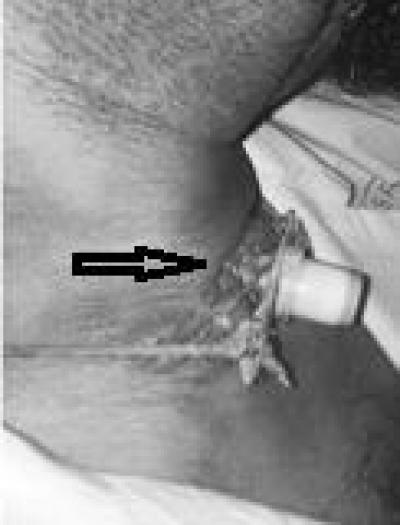

Figure 1: The figure shows a) the patient’s tracheostomy tube protruded anteriorly from stoma due to presence of hypertrophic scar (arrow)